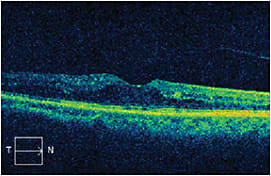

Six weeks after combination therapy, the CFT had decreased to 352 µm and visual acuity had improved to 20/60-2 (Figure 2). The swelling remained stable for 3 months (Figure 3), after which the CFT increased to 546 µm.

Figure 3. Three months post combination therapy.